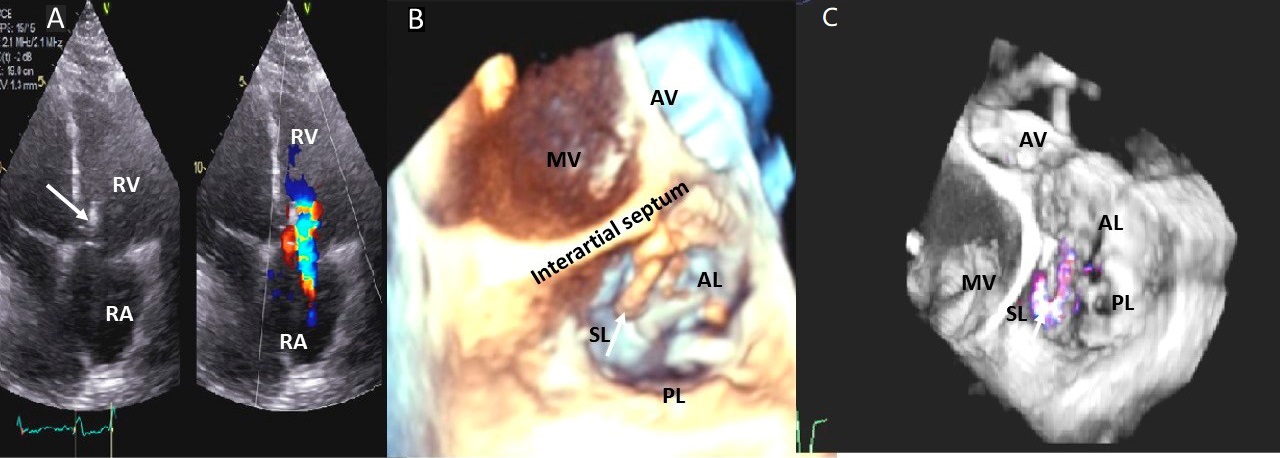

Examples of valvular injury directly from implantable cardioverter-defibrillator lead placement (Fig. 5A–C) or a permanent pacemaker (Fig. 6A–C) or endomyocardial biopsy in cardiac transplant recipients (Fig. 7A,B) are shown.

Fig. 5.Tricuspid regurgitation induced by pacemaker lead impingement. (A) 3D transthoracic echo showing and dilated RV, RA and anterior leaflet impingement by the device lead (red arrows). (B) Inspiratory systolic hepatic flow reversal (red arrows), which suggests severe TR. (C) Apical four chamber view showed severe tricuspid regurgitation. RA, right atrium; RV, right ventricle; AV, aortic valve; AL, anterior leaflet; PL, posterior leaflet; SL, septal leaflet; MV, mitral valve.

Fig. 6.Tricuspid regurgitation induced by pacemaker lead valve perforation. (A) Transthoracic 2D 4 chamber view showing pacemaker lead going through the TV leaflet (white arrow) and causing TR. (B) 3D enface view of the TV from the right atrial perspective showing the pacemaker lead going through the margin of the septal leaflet (SL) of the TV (white arrow). (C) 3D color Doppler view of the TV from the atrial perspective showing origin of TR at the site of leaflet perforation. MV, mitral valve; AV, aortic valve; PL, posterior leaflet; AL, anterior leaflet

To reduce the incidence of cardiac pacemaker lead placement related TR, TEE-guidance was found safe and feasible during PM or ICD implantation and resulted in steps to optimize lead position. At discharge, lead position was stable, and TEE-guided implantation was associated with less worsening of TR than standard lead implantation guided by fluoroscopy [54]. In this study, leads were placed according to a dedicated echo protocol with focus on a trans gastric en face view of the tricuspid valve targeting a stable lead position in a tricuspid valve commissure (preferentially postero-septal) and an apical ventricular lead position [54]. Echocardiography, particularly 3D TEE) is helpful in identifying and defining the mechanism of pacer-lead-related TR [55] (Fig. 6).